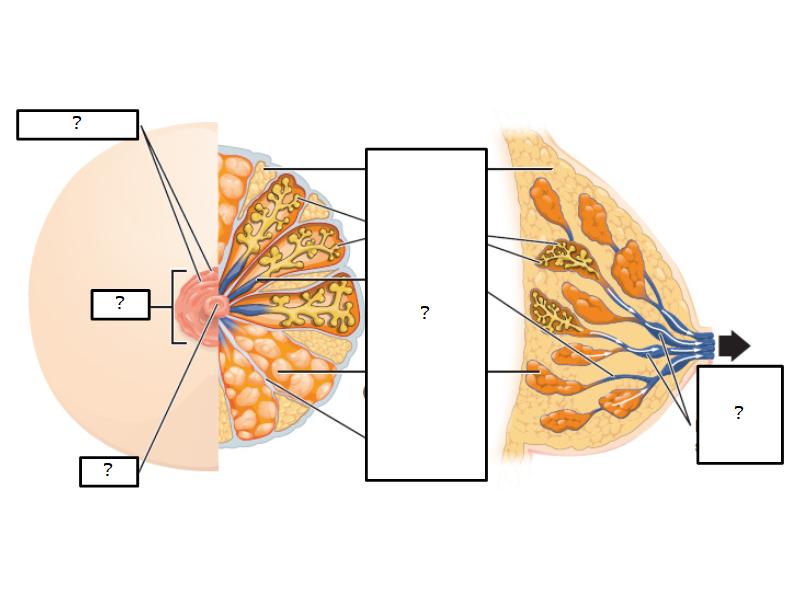

Mammary gland

Write short notes describing the structure of the mammary gland.

Mammary gland

- Compound tubuloalveolar gland

- 12 - 20 glands

- Each with own lactiferous duct

- Each with own lactiferous sinus

- Opens on skin at apex of nipple

Structures

List the structures and cells found in the mammary gland.

Structures

- Lactiferous sinuses

- Stratified squamous near opening on skin

- Stratified cuboidal other parts

- Lactiferous ducts

- Stratified cuboidal

- Myoepithelial cells

- Underlie lactiferous ducts in most areas

- Basal lamina

- Separate epithelial components from stroma

Morphology

What are the main morphological features of the nipple?

(4)

Morphology

- Covered with skin

- Consists of dense collagenous connective tissue

- Interlaced with smooth muscle fibres

- Contains openings of lactiferous ducts

Skin

- Keratinized stratified squamous epithelium

- Sebaceous glands

Stroma

- Collagenous connective tissue

- Irregular dense connective tissue

- Smooth muscle

- Fibres and bundles

- Lactiferous sinusses

- Stratified cuboidal epithelium